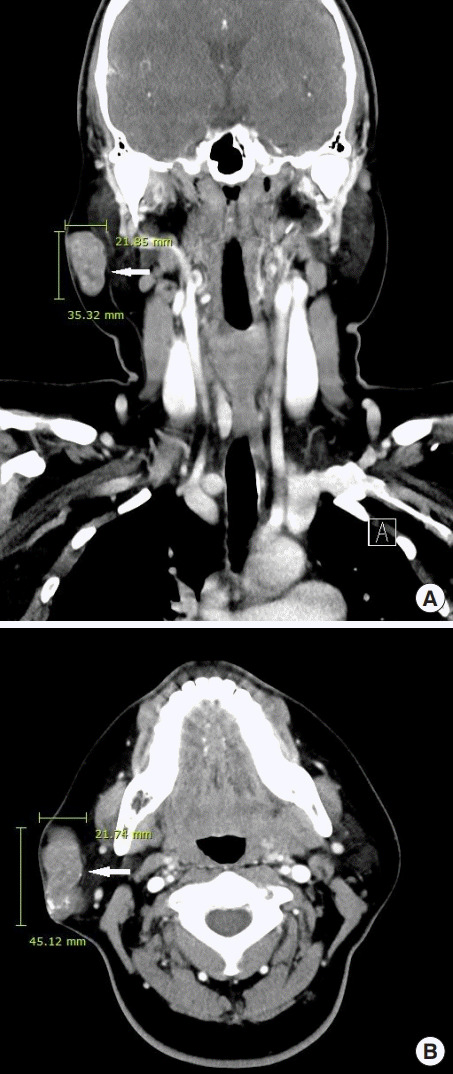

進行超聲檢查以確定腫塊是否為腮腺腫瘤,并顯示與腮腺分離的異質(zhì)腫塊(圖 2)。 進行了頸部對比增強計算機斷層掃描和超聲引導(dǎo)穿刺活檢。 在右下頜角,它表現(xiàn)為邊界清楚、分葉狀和不均勻強化的腫瘤,在皮下脂肪層和淺表肌肉腱膜系統(tǒng)中有鈣化部分(圖 3)。 穿孔活檢顯示與毛母質(zhì)瘤一致的特征,并且在超聲引導(dǎo)下對頸部淋巴結(jié)進行抽吸活檢時未發(fā)現(xiàn)腫瘤細胞。

圖 3:頸部對比增強計算機斷層掃描的冠狀 (A) 和軸位 (B) 視圖顯示右腮腺區(qū)域(箭頭)中邊界清楚、分葉狀、不均勻的病變。